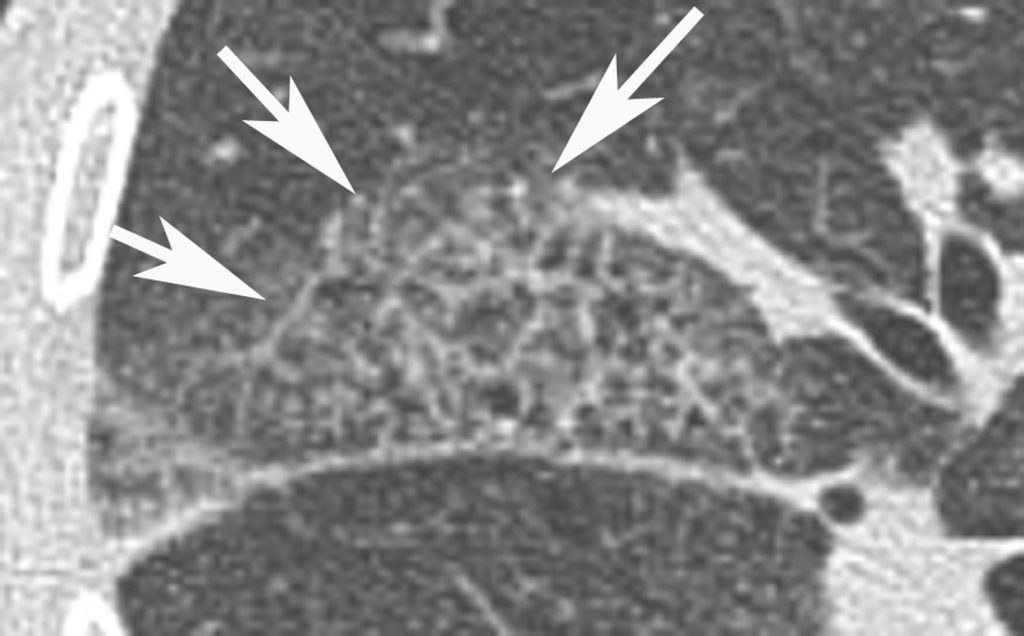

Fig. 97.5. Pneumopathie d’hypersensibilité.

Agrandissement sur le sommet droit d’une coupe frontale. Micronodules à limites floues (flèches) de distribution diffuse dans les deux poumons. Leur topographie centrolobulaire est attestée par l’absence de micronodules sous-pleuraux (têtes de flèches).

Source : CERF, CNEBMN, 2022.